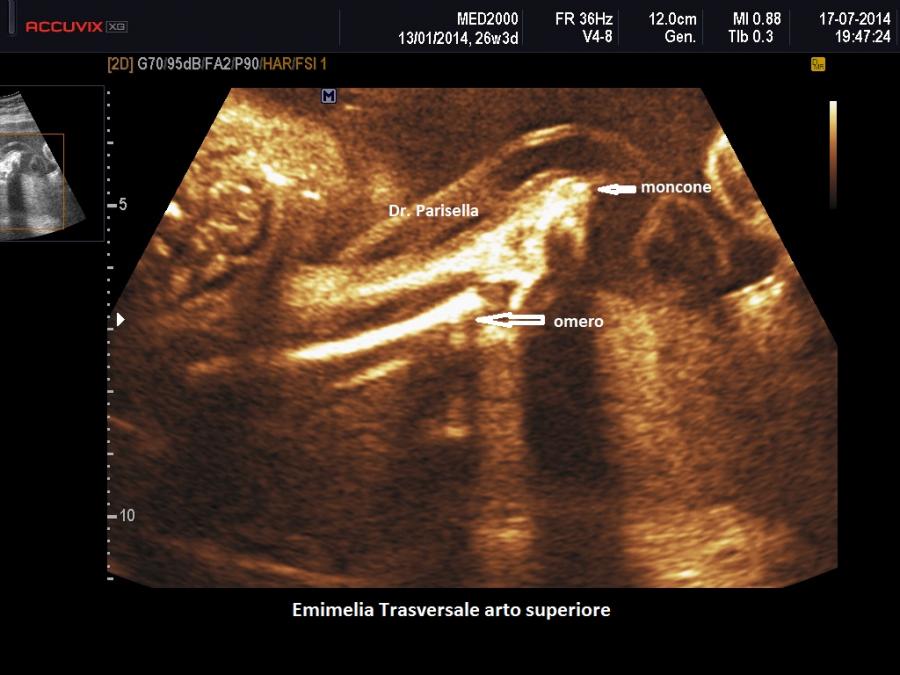

trasversale o trasversa quando manca completamente la parte distale di un arto e può essere presente un moncone che ricorda quello di un'amputazione.